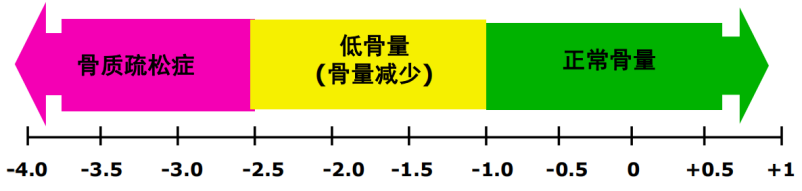

饮食上应多吃钙和维生素 D 含量较高的食物,如蔬菜、鱼类、蛋类、豆腐、菌菇、燕麦、奶制品等。

根据自身情况选择运动方式,进行适量的室外运动,既可负重锻炼,增加肌群的力度和协调性,又可吸收光照促进维生素 D 的合成转化,利于钙的吸收。

维生素 D 除了来源于食物,还依靠阳光中的紫外线照射皮肤而合成。

充足日照,建议 11:00~15:00,暴露四肢及面部皮肤于阳光下 15~30 min(取决于日照时间、纬度、季节等因素),2 次/ 周,以促进体内维生素D的合成。

尽量不涂抹防晒霜,以免影响日照效果,但需注意避免强烈阳光照射,以免灼伤皮肤。